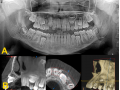

Rozległa torbiel zawiązkowa żuchwy

Paulina Adamska, Maria Mikołajska, Anna Janowska, Anna Starzyńska